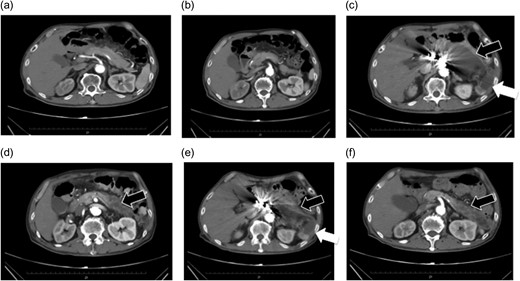

(a and b) Preoperative contrast-eCT. (c and d) eCT performed on postoperative day 13. A cyst is seen on the pancreatic tail (black arrow), while no contrast effect is seen in the spleen (white arrow). (e and f) CT performed on postoperative day 21. The pancreatic cyst has started to shrink. Part of the spleen becoming necrotic does not conflict with an etiology of ischemia due to embolization of the splenic artery.

Follow-up eCT on postoperative day 13 showed expanded necrotic and cystic areas compared to immediately after onset. Infected necrosis was suspected. Meropenem 1.0 g/day and a protease inhibitor, gabexate mesilate 2500 mg/day, were administered. eCT on postoperative day 20 showed shrinkage of the pancreatic necrosis and cyst.

The patient did not have preoperative risk factors for pancreatitis. Additionally, CT images taken at the arterial and late phases (180 s) did not show a contrast effect in the splenic artery distal to the embolism or the spleen. Pancreatitis occurred immediately after the arteries perfusing the pancreas were surgically embolized. Therefore, we diagnosed pancreatitis due to reduced pancreatic blood flow secondary to embolization (Fig. 2).